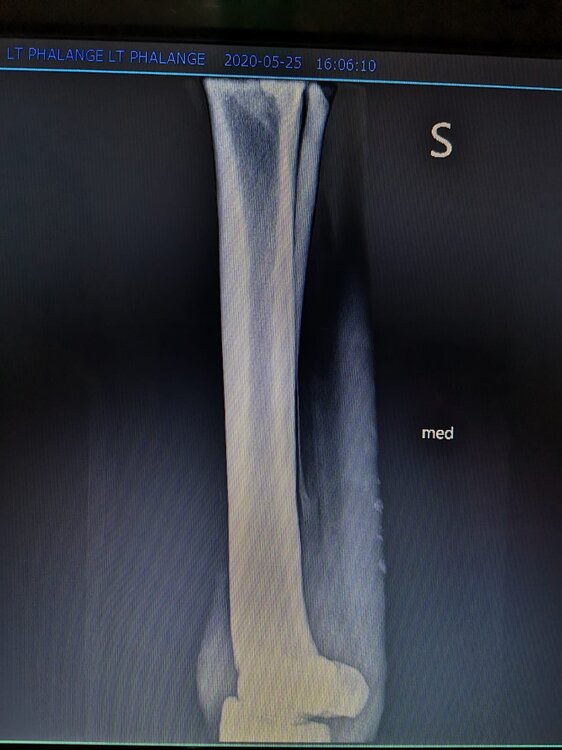

Salve volevo chiedervi qualche informazione in merce tò a un problema che ho avuto con la mia puledra. Qualche settimana fa mentre stavo lavorando alla corda è scivolata urtato l'arto posteriore sinistro. Arrivati in box ho messo dell'acqua a pressione perché si era gonfiato sia il nodello sia il pastorale. Già l'indomani l'arto era sgonfio ritornato normale, quindi ho continuato a lavorarla. Ma dopo qualche giorno di lavoro alla corda leggerissimo, al rientro in box ho notato che sia il nodello che il posturale gonfiavano nuovamente. Allora ho chiamato il veterinario che ha detto che la cavalla aveva una lussazione e mi ha insegnato come cura una fasciatura con della creta per 24h per cinque giorni e un antinfiammatorio. Dopo un paio di giorni la fasciatura ha fatto come delle vesciche e il gonfiore è aumentato dal pastorale alla garra. Abbiamo chiamato un altro veterinario abbiamo fatto vedere anche a lui la cavalla e diceva che poteva essere la frattura del ditino, ma si dovevano fare le lastre per essere sicuri. Ora abbiamo fatto le lastre e il radiologo dice che c'è dell'infiammazione ma non c'è niente di grave. Il veterinario,viste le lastre dice che deve essere operata. Allora abbiamo consultato un'altro veterinario che dice che la cavalla non ha assolutamente niente. Ora io vi allego le radiografie, datemi un vostro parere perché non só più cosa fare. Grazie